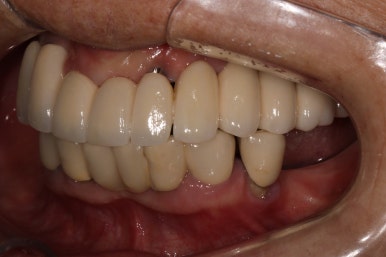

앞에서 볼 땐 많이 테가 안날수도 있겠지만...

어금니 좌측

좌우측 측면 사진 비교시, 아래 어금니 임플란트로 깔끔하게 메꿔진 빈 공간이 인상적입니다!